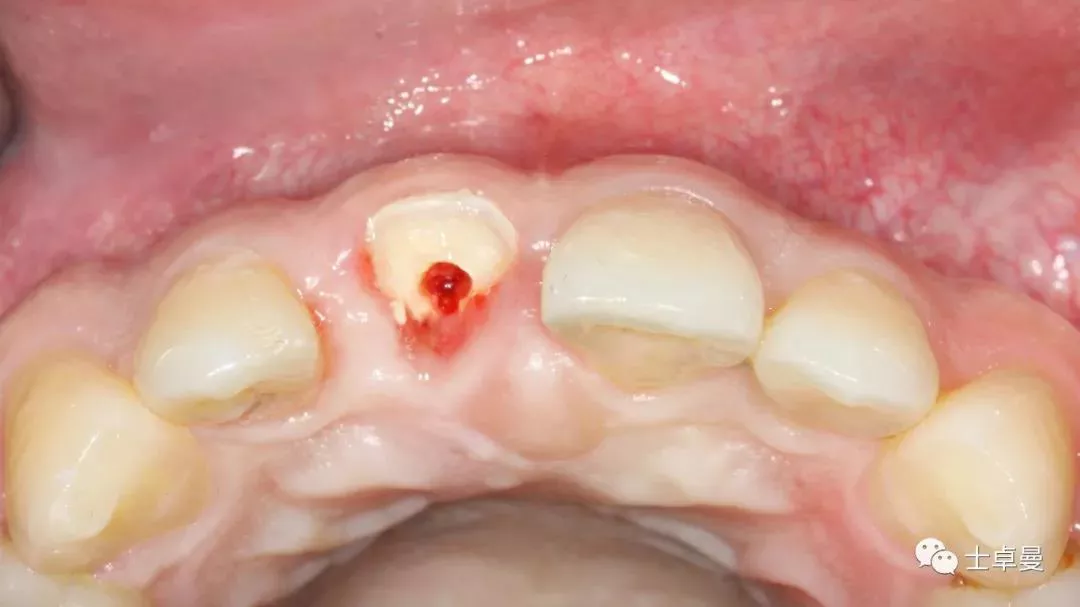

保留唇侧牙片

牙周探针探查牙片位置及松动度

· 盾技术唇侧牙片的制备要求:

▷ 切端位于龈下2mm-3mm,平齐唇侧牙槽嵴顶或高于牙槽嵴顶0.5mm;

▷ 根尖3mm-5mm要完全去除,避免根尖处的根管侧枝和分歧引起继发感染;

▷ 厚度1.5mm-2mm,与植体间不能有直接接触;

▷ 盾不能有松动,否则直接去除。